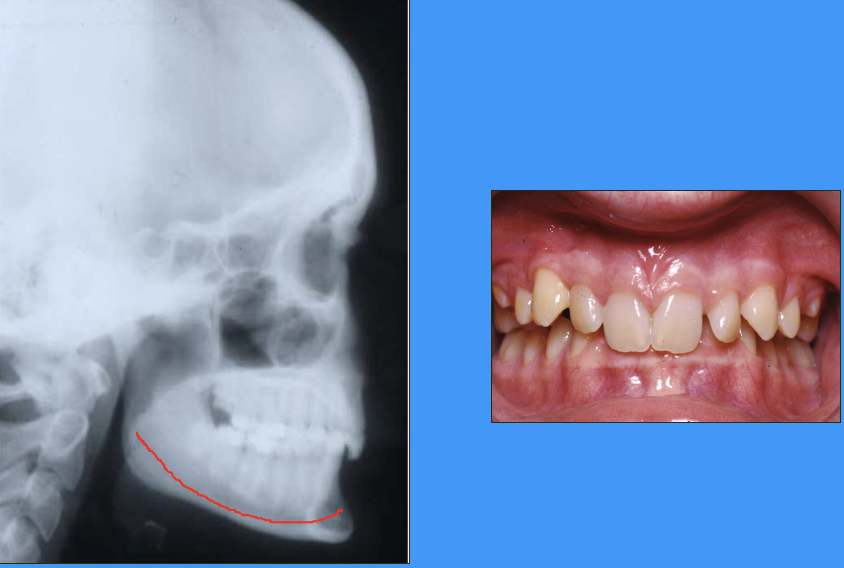

radiograph and clinical image showing anterior growth rotation of mandible

Björk’s findings pt. 1

majority had an ‘anterior’ rotation

mandibular plane angle decreases by 2-4°

increasing overbite

more skeletal class III occlusion (underbite)

leads to late lower incisor crowding?

genetic link?